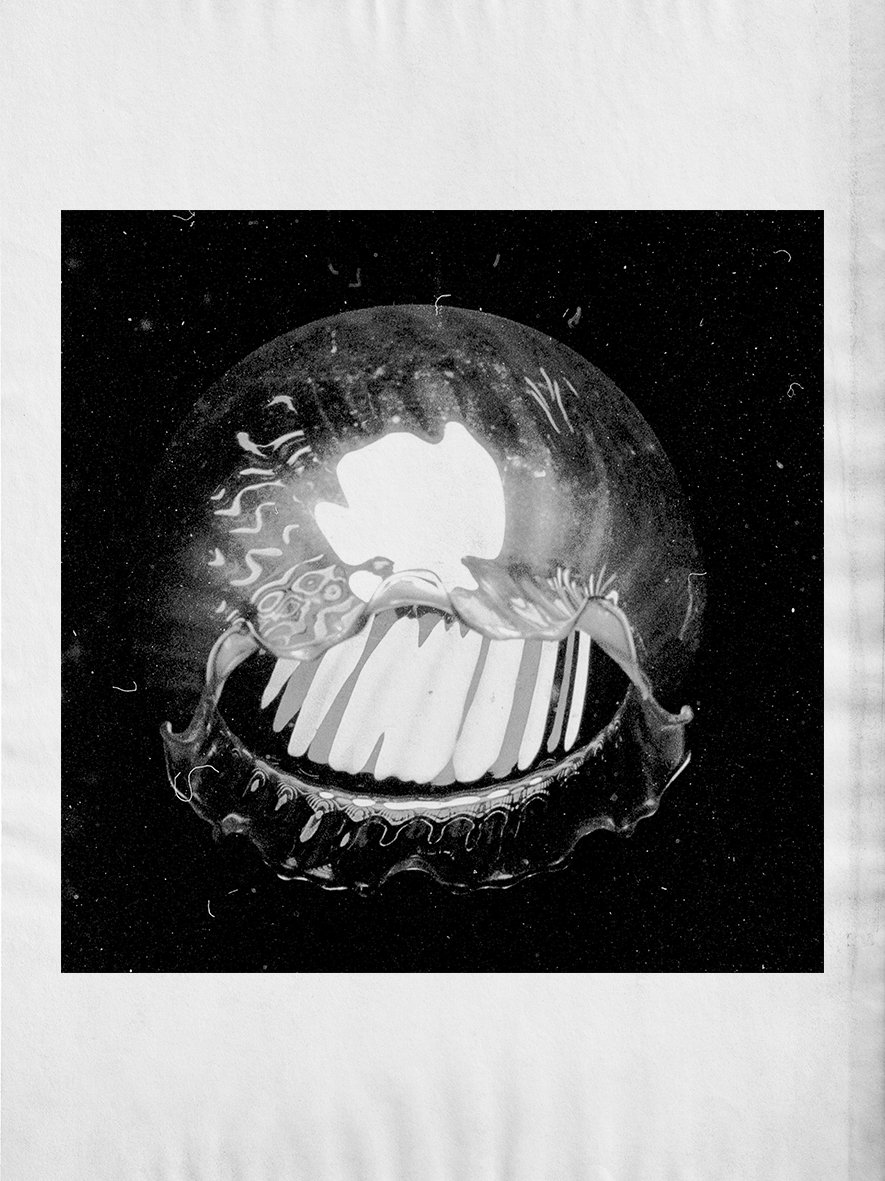

Ma première crise d’asthme m’a révélé la fragilité de l’équilibre de ma respiration, celle à qui je ne portais aucune attention jusque-là. Ce souffle qui m’accompagnait sans discontinuité, qui imprimait son rythme binaire, inspiration expiration, s’était soudain enrayé. J’étais privé de cet air illimité et invisiblequi habituellement me traverse. En nous traversant l'air anime, porte et met en mouvement. Soudain c'est la sensation d'être prisonnier de son propre corps, d'avoir les poumons pris dans un étau dont la pression ne faiblit pas, la cage thoracique n’a jamais aussi bien porté son nom. Les poumons, paroi poreuse entre le monde intérieur et extérieur, se transforment en muraille impénétrable. Seules les vaporisations quotidiennes de Ventoline, produit à la force libératrice, peuvent stopper cette inertie et faire sauter le verrou sur la poitrine.La crise d’asthme mime, de façon répétitive, la suffocation. Elle ne fait que mimer, son sort comme celui de toute crise c’est de ne durer que le temps d’atteindre son paroxysme avant sa résolution. En l’absence de crise, aucun signe ne permet de constater sa présence, elle ne laisse aucun stigmate, l'asthmatique est une personne ordinaire. La crise n’est pas réelle, tant qu’elle ne se manifeste pas.